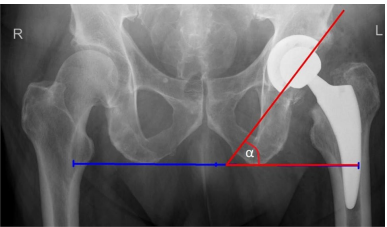

髋臼倾角 (Acetabular inclination, AI)/外展角

髋臼倾角也称为外展角 (abduction angle)。放射学AI在前后位X线片上测量。它是经坐骨结节线 (transischial line) 与穿过臼杯边缘的线之间的夹角。AI影响活动范围和髋臼部件的磨损。当外展角小于45°,屈曲和外展会减少。另一方面,AI超过45°会减少外展和旋转。当AI超过45°时,髋臼聚乙烯的磨损也会更高。如果没有进一步的研究,无法明确说明AI的安全范围是多少。

髋臼倾角测量。α - 经坐骨结节线与穿过臼杯边缘的线之间的夹角